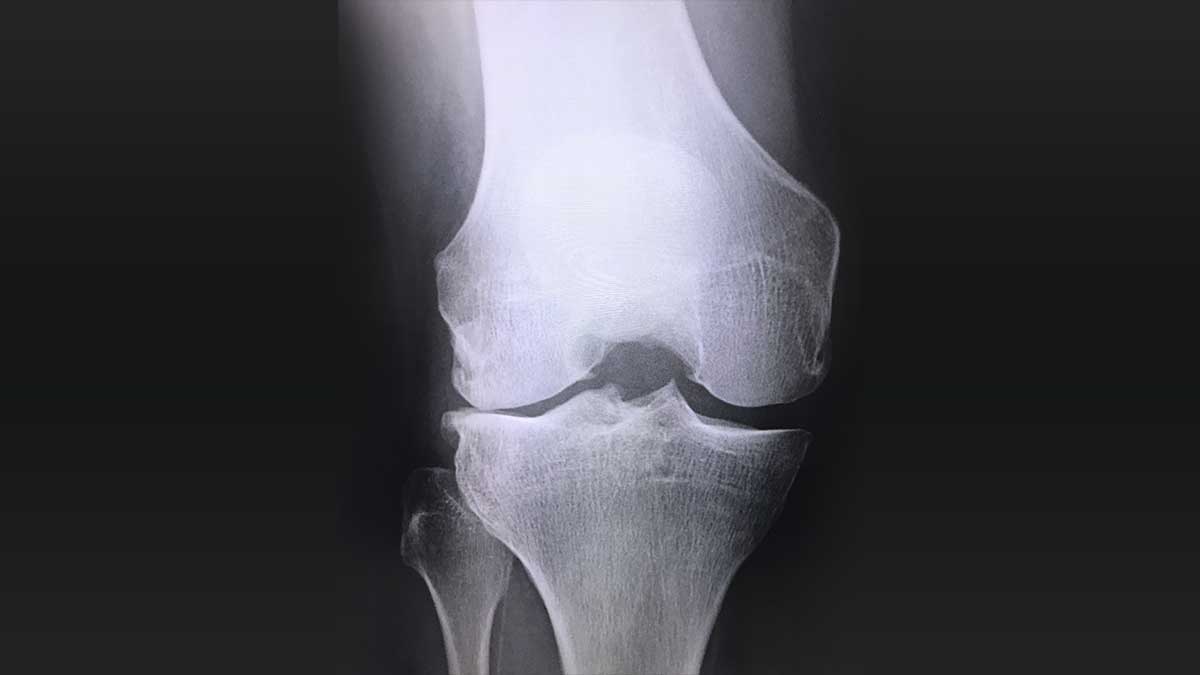

ひざの再生医療(変形性関節症)

これまで変形性膝関節症に対する治療は、理学療法や薬物療法などによる保存療法と、人工膝関節へ置き換える手術療法がメインでしたが、2014年に再生医療に対する法整備が進んだこともあり、再生医療はより身近なものになっています